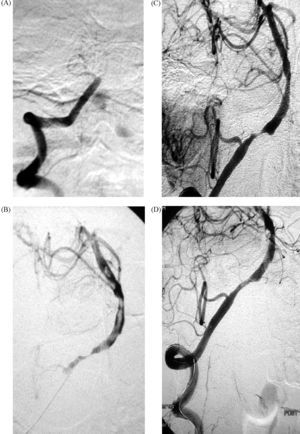

Estas han sido algunas de las razones por las que el tratamiento endovascular en la fase aguda del ictus isquémico está adquiriendo cada vez más importancia como complemento a la trombólisis intravenosa en los casos en que ésta está contraindicada o no ha sido eficaz. El estudio PROACT II demostró la eficacia del tratamiento trombolítico intraarterial con prouroquinasa en las oclusiones de la ACM en una ventana terapéutica de 6h, y consiguió un beneficio absoluto del 15%8. El intervencionismo neurovascular (INV) (fig. 1) ha demostrado, en amplias series de pacientes, su eficacia y seguridad y, en algunos trabajos, consiguió mayores tasas de recanalización arterial que el tratamiento intravenoso9. El INV incluye técnicas de trombólisis intraarterial, angioplastia con implantación de stent, disrupción y extracción mecánica del trombo8,10–12. También está la posibilidad de aplicarlo de forma secuencial tras la trombólisis intravenosa en los casos en que ésta no ha sido eficaz13.

A: arteriografía digital selectiva de arteria vertebral (AV) derecha donde se aprecia oclusión completa de la arteria basilar (AB) en su segmento proximal. B: tras disrupción mecánica del trombo con el microcatéter y administración local de 5mg de t-PA, se consigue una recanalización parcial de la AB; se aprecian múltiples defectos de repleción compatibles con trombos. C: tras la administración de otros 5mg de t-PA se consigue la recanalización completa; se visualiza una estenosis crítica en la unión vertebrobasilar. D: imagen final tras angioplastia y colocación de stent intracraneal, donde se observa una estenosis residual.